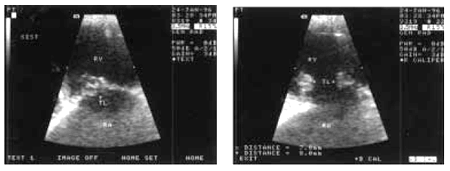

Эхокардиографическое исследование клапанного аппарата при инфекционном эндокардите имеет важное практическое значение, поскольку во многих случаях оно позволяет выявить прямые признаки этого заболевания — вегетации на клапанах, если их размеры превышают 2–3 мм. Большей информативностью (около 70–80%) в данном случае обладает М-модальное исследование. Отличаясь более высокой разрешающей способностью, оно позволяет обнаружить низкоамплитудные высокочастотные систолические вибрации, связанные с повреждением створок клапанов. Вегетации обнаруживаются в виде множества дополнительных эхосигналов, как бы «размывающих» изображение движущихся створок клапана («лохматые» створки) (рис. 9.8, а).

| Рис. 9.8. Эхокардиографические признаки вегетаций на створках митрального клапана: а-одномерная эхокардиограмма(схема); б-двухмерная эхокардиограмма (фрагмент); в-двухмерная эхокардиограмма из апикальной позиции четырехкамерного сердца |

Двухмерная эхокардиография позволяет не только визуализировать вегетации, но и оценить их форму, величину и подвижность (рис. 9.8, б, в). Подвижные вегетации имеют обычно несколько вытянутую форму. Одним своим концом они прикрепляются к створкам, а другой конец свободно перемещается с током крови, как бы независимо от движения самих створок. Например, при поражении трехстворчатого клапана вегетации то всплывают в полости ПП (в систолу), то появляются в полости ПЖ (в диастолу) (рис. 9.9).